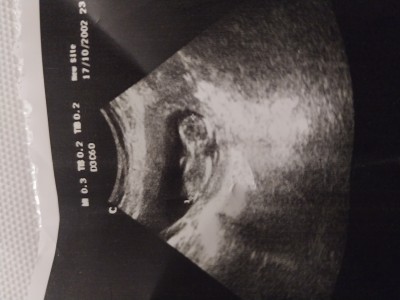

12haftalik tahmin yapar misiniz

Gebelik haftası 12

Erkeğe benziyor

Erkege benzettim. Tamamen hislerimle . Anlamam pek sjsj hayırlısı olsun canım